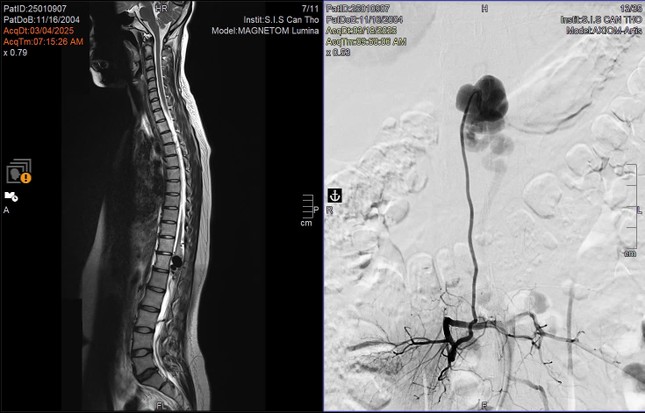

Hình ảnh kiểm tra phát hiện vị trí dị dạng mạch máu tủy ở bệnh nhân

N. được người quen giới thiệu đến bệnh viện S.I.S Cần Thơ và được chỉ định chụp cộng hưởng từ (MRI). Từ kết quả hình ảnh học, các bác sĩ phát hiện khối dị dạng mạch máu lớn chèn ép vùng tủy sống, gây phù tủy và tổn thương hệ thần kinh nghiêm trọng.

TS.BS Trần Chí Cường , Giám đốc Bệnh viện Đa khoa S.I.S Cần Thơ cho biết: "Thông thường, đường kính tủy sống khoảng 2cm. Tuy nhiên, ở bệnh nhân này, túi phình dị dạng lên tới gần 2,4 cm, chèn ép hoàn toàn vùng chóp cùng tủy – nơi có chùm đuôi ngựa chi phối vận động hai chân. Đây là nguyên nhân khiến bệnh nhân đau dai dẳng và yếu cơ tiến triển”.